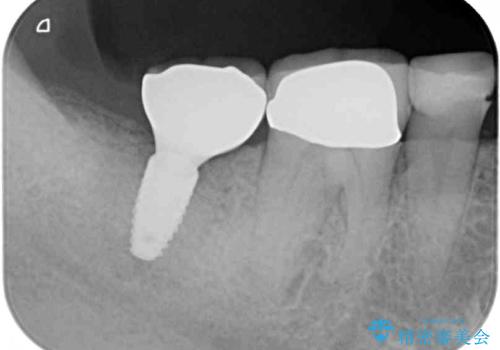

- 下顎の左右奥歯が痛みがあり、噛めないとのことで来院された患者様です。

左右ともに歯根が破折しており、抜歯が必要であったため、抜歯後にインプラント補綴治療を行うこととしました。

左側は骨欠損が著しいことが予想されるため、骨造成術並びに歯肉移植術を併用することとしました。